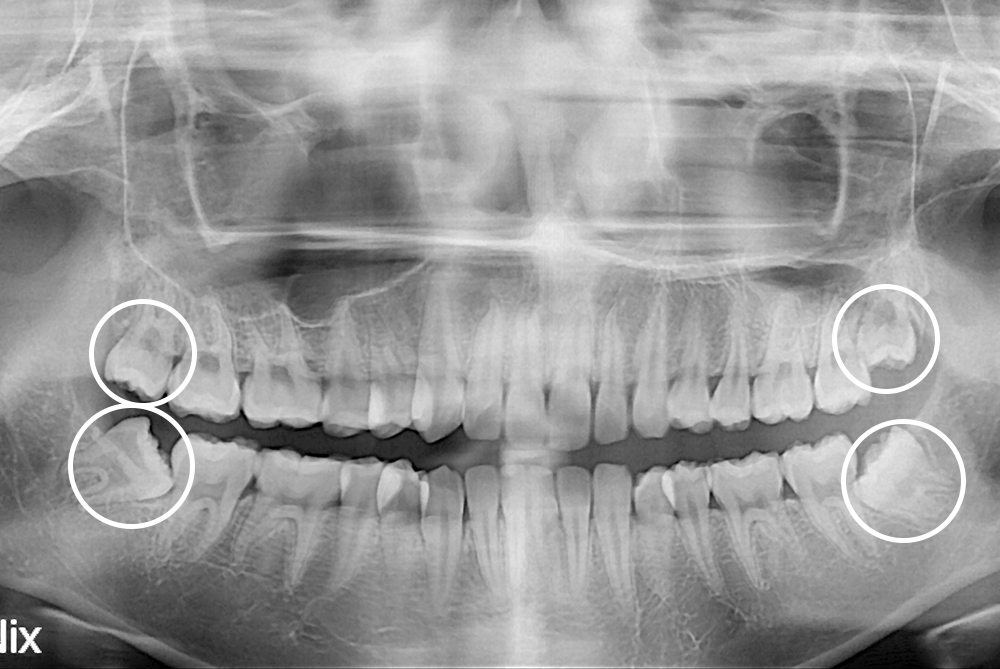

치료후 : 2020-05-09

세종치과는 구강악안면외과학 박사이신 원장님이 발치하는 치과입니다.